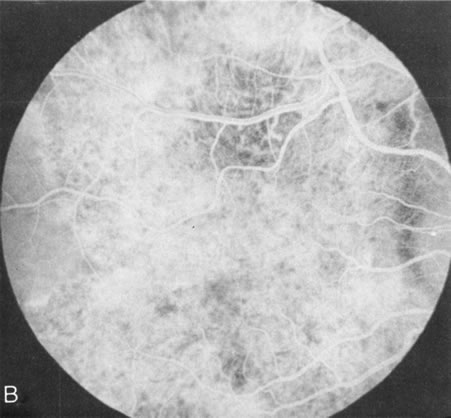

Generalized choroidal dystrophy is usually noted in middle-aged mildly symptomatic individuals who show a predominantly peripapillary or pericentral distribution of choroidal atrophy. Gradually, over the years these areas enlarge to eventually involve the entire retina. These changes are vividly seen on FA (Fig. 6).

Fig. 6. Generalized choroidal dystrophy. This 65-year-old woman gradually developed enlarging, progressive areas of choroidal atrophy over a 20-year period. When initially seen, the abnormalities were confined to the peripapillary and macular region (A,B). In a recent examination, the generalized choroidal atrophy is vividly demonstrated on angiography (C–F).